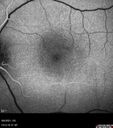

35 year old male Yesterday morning the patient woke up with poor vision in the left eye. Prior to that his vision was OK. PMHx benign. Blood pressure 154/115 mmHg. VA OD: Dcc20/16 NccJ1+ (-2) VA OS: Dcc20/40 PHNI NccJ16 IOP: TP: OD:22 OS:18 Lens clear – no uveitis Persistent fluid at 6 months required PDT laser - then fluid absorbed

Central Serous Chorioretinopathy - Expanding hot spot - photodynamic laser244 views35 year old man with acute central serous chorioretinopathy. The fluid got better then worse and the patient was treated with full strength juxtafoveal PDT and then got better.00000